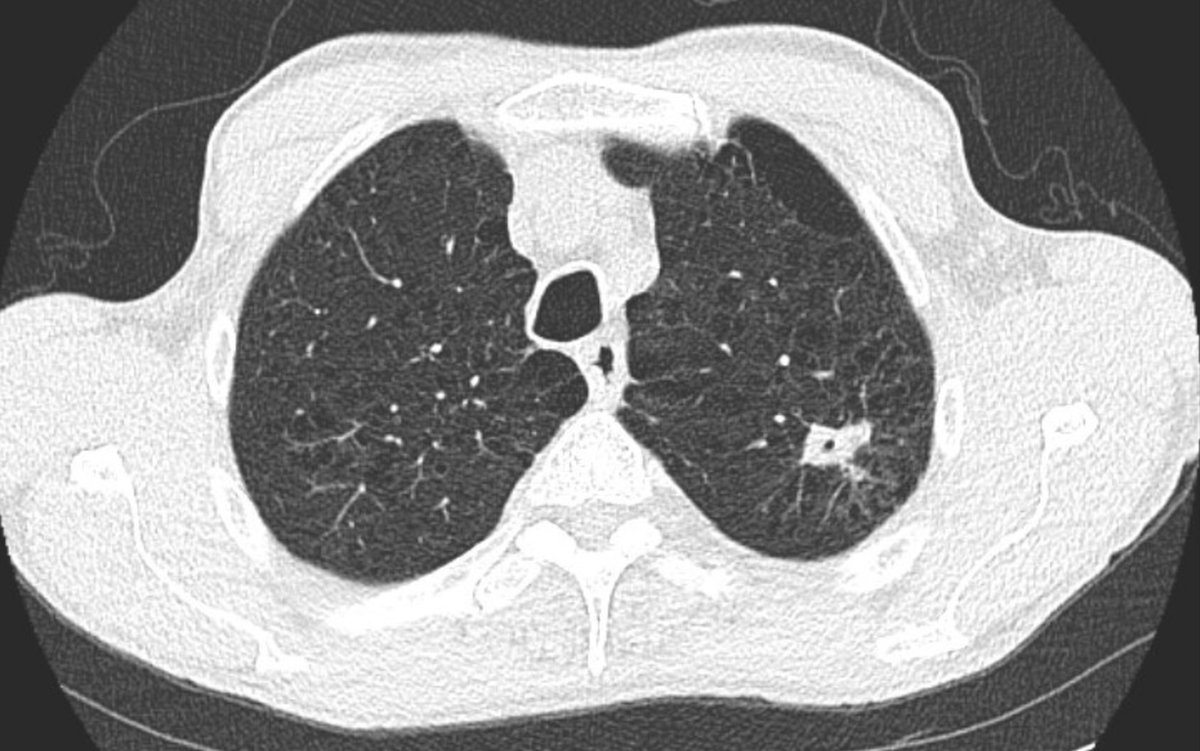

A multicenter prospective study of robotic-assisted bronchoscopy shows that RAB-guided sampling of peripheral pulmonary lesions compares favorably with results from sizable nonrobotic #bronchoscopy studies.

Read more in the August #JournalCHEST issue: hubs.la/Q03Cql920